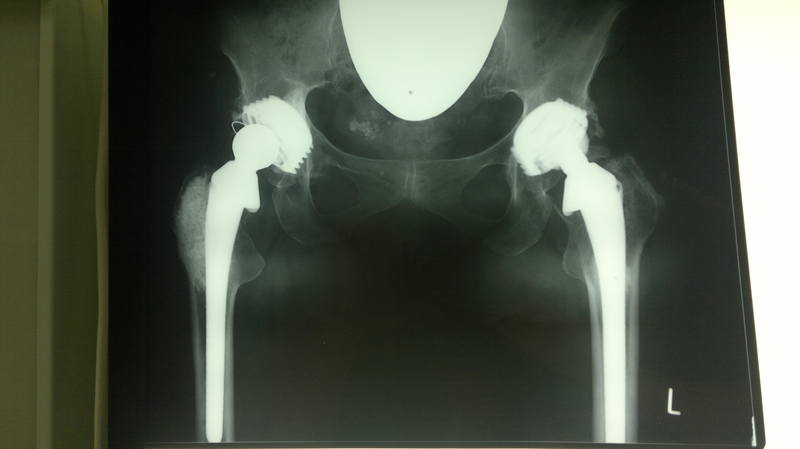

Попытаюсь разбавить зависшую на форуме тишину представлением случая, который закончился ревизионным эндопротезированием.<br /><br />Женщина 60 лет была оперирована в связи с двухсторонним диспластическим коксартрозом 3 степени 19 лет назад. Выполнено тотальное безцементное и комбинированное эндопротезирование с интервалом в 1 год. Около 1,5 лет назад появилась боль в паху, что явилось причиной обращения к ортопеду. При выполнении рентгенограммы была выявлена следующая картина:<br /><br />

<br /><br />Выставлен диагноз Состояние после двухстороннего ТЭТС. Асептическая нестабильность вкладыша эндопротеза справа. Да вот беда - эти эндопротезы уже сняты с производства... и вкладышей таких нет. Ревизионное эндопротезирование поэтому представляет непростую задачу...